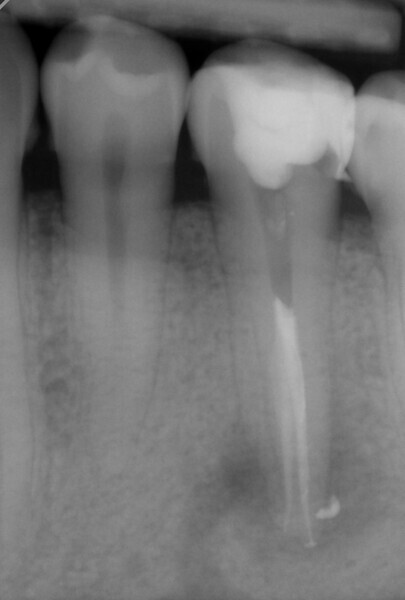

Fig. 1: Pre-op panoramic radiograph.

This was due to a special dental anatomy that had not been identified. In the middle of the root, about 13–14 mm from the cusps, the root canal split into two different canals (Vertucci Type V or deep split). This was easy to see on the initial panoramic radiograph (Fig. 1), which is why I decided to prepare the canals with HyFlex CM and HyFlex EDM files and under magnification (Figs. 2 & 3). This allowed me to follow the respective canal profiles and preserve the root canals as far as possible through optimal and centred preparation in each canal.

The treatment was performed in two appointments. The first appointment involved preparation, cleaning and interim medication with calcium hydroxide. After applying the dental dam to isolate the working field, the 25/0.12 HyFlex EDM Orifice Opener and the 10/0.05 HyFlex EDM Glidepath files were initially used to open the canal and create the glide path. The actual preparation was performed with 15/0.04 and 20/0.04 HyFlex CM files followed by the 25/~ HyFlex EDM OneFile (Fig. 4). During treatment, the canals were rinsed extensively with CanalPro sodium hypochlorite and EDTA and dried with the corresponding HyFlex paper points and the practical, flexible Surgitip endodontic aspirator tips (COLTENE) before application of the calcium hydroxide dressing (Fig. 5). Ultrasonic activation was also used to enhance the effect of the irrigation solutions.